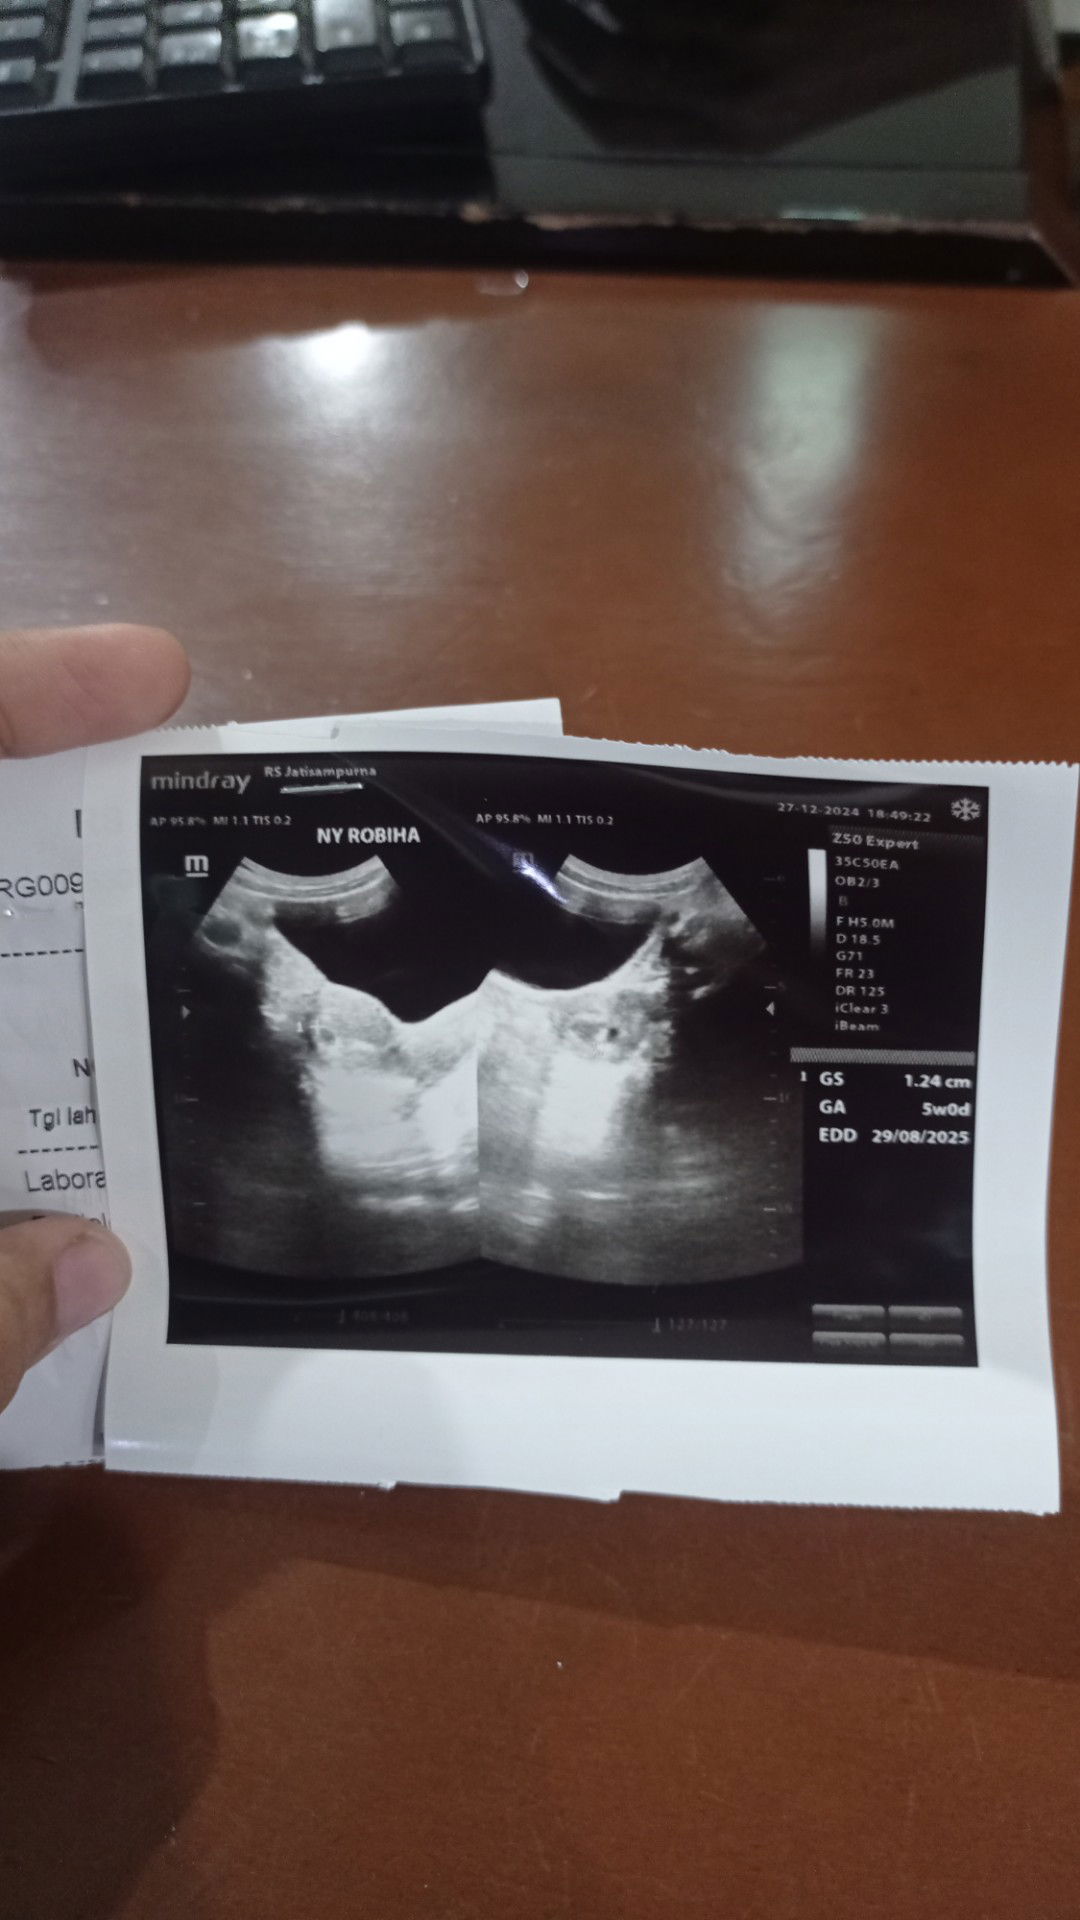

Saya kehamilan kedua Udh 4 kali USG dan tiap USG beda terus usianya Pertama di RS sama obgyn (5w) Kedua klinik sama bidan (7 w) ketiga klinik sama obgyn (8 w) Keempat puskesmas sama bidan (jadi 5 w) Wajar g si Bun? Atau salah perkiraan karena beda alat?🥲aku Overthinking jadinya. Tapi kata bidan puskesmas, terakhir USG itu aku kurang cairan, jadi USG g begitu jelas. Itu foto USG terakhir kali belum lama ini #Needadvice #bantujawab